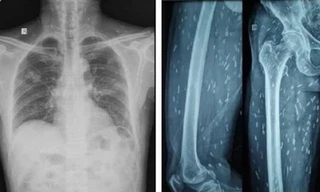

TPO - Ngày 23/8, BS Phạm Định Chương, khoa Nội Thần kinh, Bệnh viện Hoàn Mỹ Sài Gòn cho biết, tại đây vừa tiếp nhận một trường hợp bị rò động mạch cảnh xoang hang. Trước đó, bệnh nhân có biểu hiện đau đầu, nhìn mờ, triệu chứng ngày càng tăng.

TPO - Một bé gái 17 tháng tháng đột ngột bị méo miệng, mắt nhắm không kín sau khi bị chảy mũi, ngạt mũi. Triệu chứng tưởng như bình thường. Tuy nhiên, khi gia đình đưa đến bệnh viện kiểm tra thì tá hỏa phát hiện bé bị bị viêm tai xương chũm biến chứng tổn thương thần kinh số VII ngoại biên có thể gây liệt mặt.

TPO - Ths.BS Dương Văn Tâm - Trưởng khoa Liệt vận động và Ngôn ngữ trẻ em (Bệnh viện Châm cứu Trung ương) cho hay, do thời tiết lạnh trong vòng hơn 1 tuần qua, số bệnh nhân đến khám và nhập viện do bị liệt mặt gia tăng .Bình quân tại bệnh viện mỗi ngày có khoảng 20-30 bệnh nhân đến khám và điều trị méo mồm, liệt mặt.